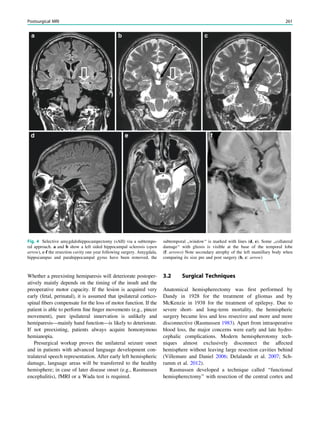

Fig. 2 Dural a. v. fistula. A 53-year-old man presented with two tonic–

clonic seizures. MRI shows circumscribed edema in the left frontal lobe

(a, hollow arrow) and an abnormal vessel running in the left sulcus

rectus (c, arrow). The digital subtraction angiogram of the left internal

carotid artery shows a frontobasal dural arteriovenous fistula fed via

ethmoidal arteries (d, arrow) and confirms the abnormal vessel as a

draining vein (e, arrow)